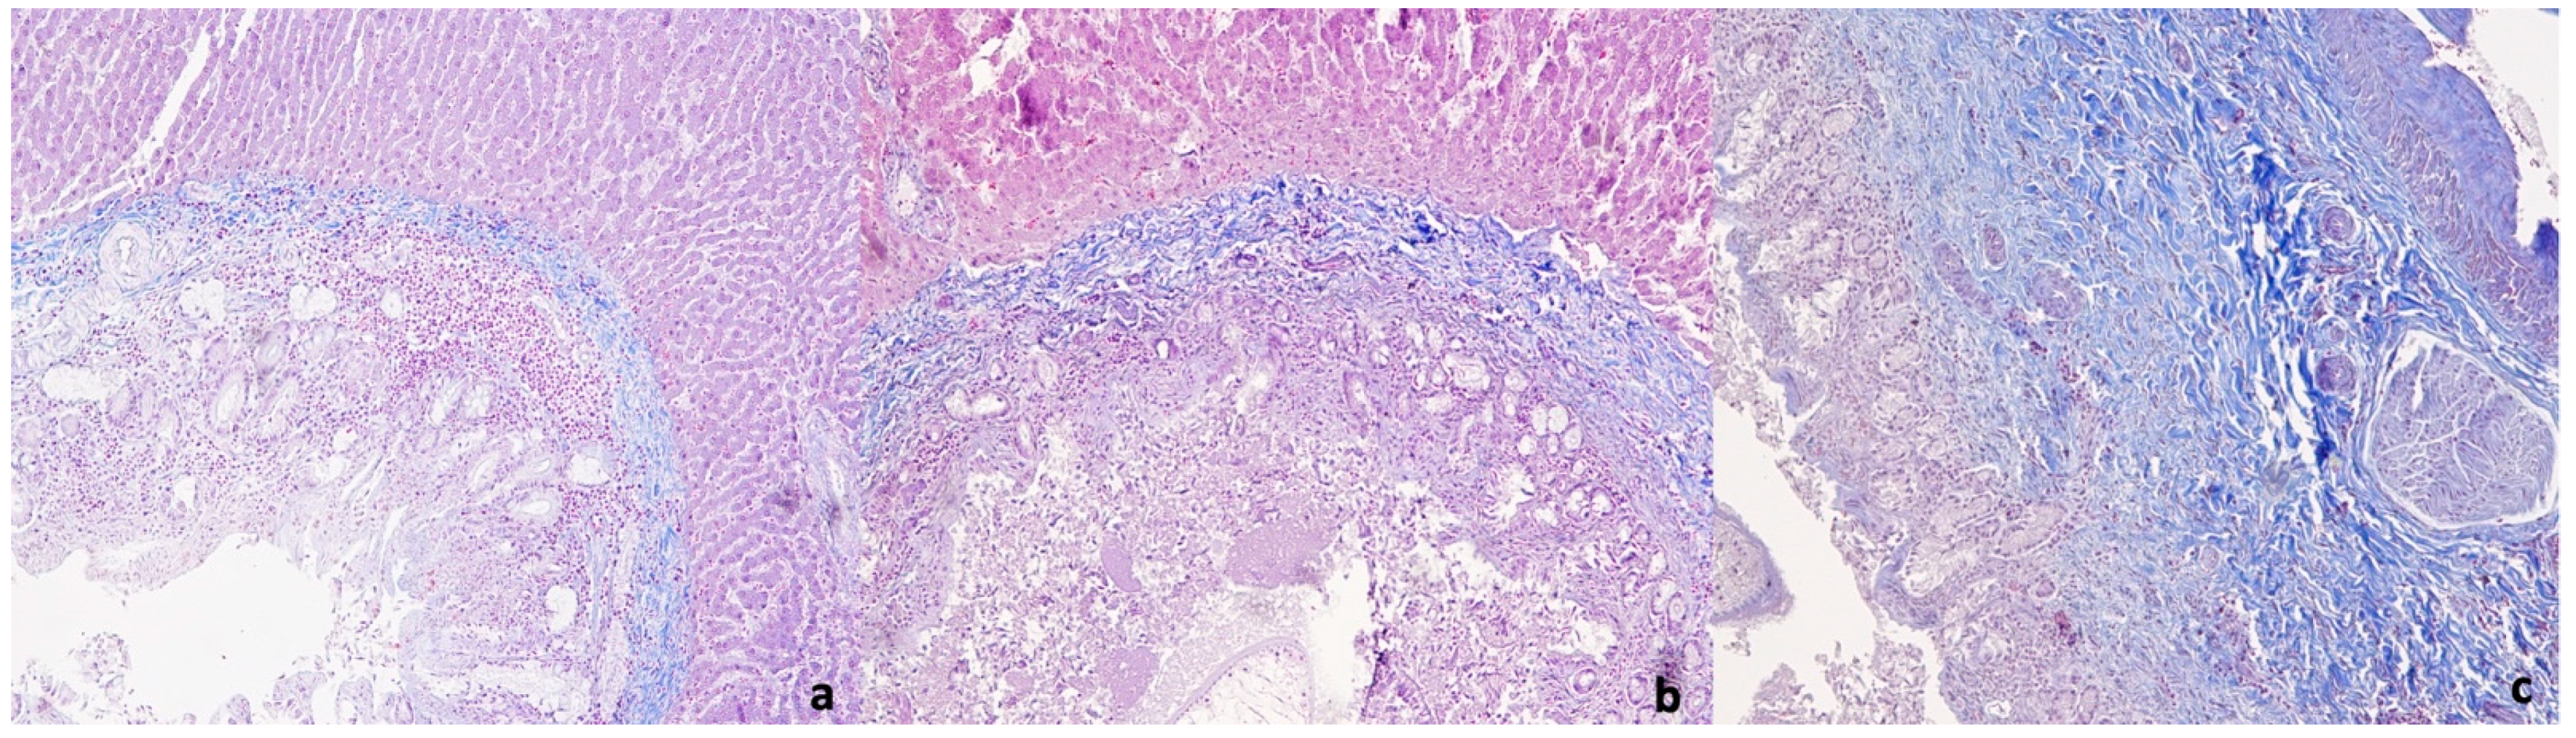

3.3. Histological Examination

4.2. Gross and Histological Examination